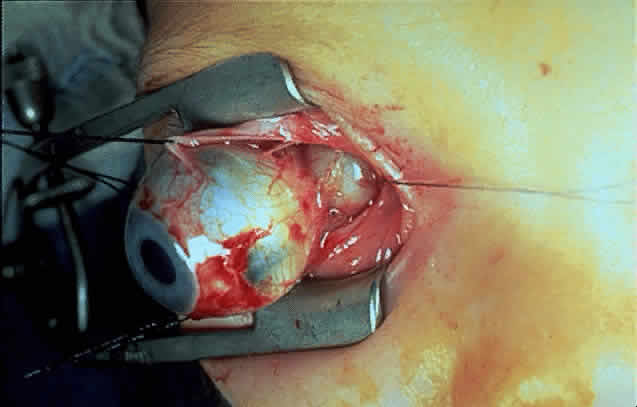

| A key factor affecting prognosis is the effect of the tumor on neighboring

brain structures. Consequently, optic gliomas confined to the optic

nerve typically have a good prognosis. However, approximately 21%3 to 70%2 of pure optic nerve gliomas may progress, and a mortality rate of 5.3%3 from intracranial extension with central nervous system involvement has

been described. Based on his clinical experience, Miller71 suggested that patients with a relatively benign prognosis were likely

to present with mild proptosis, optic disc pallor, and neurofibromatosis. Patients

with more severe proptosis, optic disc swelling, and no

evidence of neurofibromatosis were more likely to have symptomatic tumor

growth. Patients who undergo excision of their optic nerve gliomas

have a recurrence rate of 0.5%.3 The recurrence rate after excision of an intraorbital glioma is doubled

by a patient history of neurofibromatosis.2 Incomplete excision of the optic nerve glioma can still be associated

with low mortality.99 Some authors, however, have described intracranial extension occurring

after incomplete excision, with subsequent invasion of the chiasm and

third ventricle ultimately resulting in death.24,25 Tumor extension to the chiasm is associated with an increase in mortality to approximately 28%.3 Interpreting the natural history of optic chiasmal gliomas is complicated by the potential existence of two types of chiasmal gliomas. An anterior type is believed to originate within the anterior visual system and may or may not infiltrate the hypothalamus and adjacent neural tissue. A posterior type is believed to originate in the hypothalamus and secondarily invades the chiasm.18 Multiple reports concerning both visual and radiologic stability with conservative follow-up can be found in the literature.18,32,100–103 However, of 125 reviewed cases of chiasmal glioma that were untreated or partially excised, recurrence or progression of tumor was noted in 64%. Tumor-related mortality during a mean follow-up period of 10 years was 17%.3 Clinically, chiasmal glioma patients who have neurofibromatosis, a generalized enlargement of the optic pathway as opposed to a globular appearance, and no involvement of adjacent neurologic structures may have a better clinical course.25,71,73 Adjacent hypothalamic or third ventricle involvement is noted in 46% of chiasmal gliomas.3 Patients with a glioma involving the chiasm and the hypothalamus or third ventricle have an overall mortality of 51% with no treatment or with partial excision (mean follow-up approximately 15 years).3 Patients who do not develop hydrocephalus may have a somewhat better chance of survival.2 Chiasmal gliomas that have undergone malignant evolution have been reported.104 Controversy exists as to whether patients with NF-1-associated glioma have a better prognosis. In a series of 114 patients with optic gliomas, pure optic nerve lesions were noted in 80% of NF-1 patients compared with 16% of patients with gliomas without NF-1.21 Because of the anterior location of these tumors, investigators suggested a better prognosis for neurofibromatosis-associated gliomas.21,84 Other series have not demonstrated a significant difference in tumor location or ultimate prognosis for neurofibromatosis glioma patients.2,3,105 Imes and Hoyt106 noted similar mortalities between patients with NF-1 chiasmal gliomas and those without NF-1. In the Imes and Hoyt series, however, six of the nine NF-1 glioma patient deaths were related to secondary tumors such as sarcomatous degeneration of peripheral neurofibromas and malignant gliomas of the brain.106 Currently, conclusive evidence does not exist for establishing a different prognosis for NF-1-associated gliomas.3 The first surgical removal of an optic nerve glioma was performed by Wishart in107 In a 1989 national clinical trial of 106 patients with unilateral gliomas initially confined to the orbital portion of the optic nerve at study entry, local progression was noted in 20% without treatment, in 29% after incomplete surgical excisions, and in only 2.3% after apparent complete excision.108 Since children with optic gliomas can maintain useful vision for years,2,3 surgical therapy is usually reserved for potentially resectable tumors confined to the orbital or intracranial portions of the optic nerves after the development of blindness or severe proptosis, or when tumor extension along the intracranial portion of the nerve threatens the chiasm.109,110 Because of the risk of visual loss as well as damage to surrounding neurologic structures, surgical intervention for gliomas involving the optic chiasm is usually considered only for obtaining a biopsy specimen of the chiasm in specific cases or for relieving hydrocephalus.71,110,111 Additionally, some benefit from debulking large exophytic chiasmal gliomas and decompressing the anterior visual pathways has been described.112 Wisoff17 noted clinical remission and relief of neurologic symptoms after radical surgical excision of chiasmatic-hypothalamic tumors. Enhanced survival and clinical stability or improvement of chiasmal glioma patients has been described after radiation therapy.113–116 Flickinger and associates115 found stabilization or improvement of vision in 86% of 32 optic chiasm or nerve glioma patients evaluated with a mean follow-up of approximately 10 years. They also observed that conservative management with observation and no radiation therapy was unsuccessful in many chiasmal glioma patients. They recommended a radiation dose of 45 to 50 Gy to the 95% isodose line using 1.8 Gy fractions, or a biologically equivalent dose using smaller fraction size, for optic chiasm glioma. Horwich and Bloom116 described a beneficial effect of radiotherapy for patients with optic glioma and progressive disease. Of their 29 patients, 26 (90%) remained free of progression with a median follow-up of 10 years. Visual acuity improved after treatment in 43%, was stable in 48%, and deteriorated in 9%. After radiation therapy with 5140 cGy over 6 weeks, Furuya and colleagues117 reported a marked reduction in the size of a posterior optic glioma in a 6-year-old child. Many authors have advocated radiation therapy only for patients with chiasmal glioma who have progressive visual loss, documented tumor growth, hypothalamic dysfunction, or hydrocephalus.18,33,61,102 Hoyt and Baghdassarian92 found that radiotherapy produced no visual benefit, attributing any favorable responses to possible spontaneous improvement. Imes and Hoyt106 found an optic glioma mortality rate of 29% for patients treated with radiotherapy but only 7% for those followed conservatively. Packer and co-workers118 reported on their experience with radiation therapy in 21 cases of surgically verified chiasmal gliomas. They noted a high incidence of mortality and morbidity from progressive disease, and possible morbidity due to treatment. Visual improvement after radiation treatment was uncommon in their series. Although some reports suggest a short-term benefit from radiotherapy for patients with progressive chiasmal gliomas, evidence that radiotherapy contributes to long-term survival or visual function is debatable. Alvord and Lofton's2 review of 542 cases of chiasmal gliomas mentioned in the literature did not demonstrate any benefit from radiation in terms of ultimate recurrence or survival; however, radiation therapy did appear to delay disease progression for several years. Actuarial analysis showed a higher rate of death or tumor progression in patients with chiasmatic glioma and hydrocephalus who received less than 45 Gy of radiation therapy compared with those who received more than 45 Gy. Dutton3 assessed 511 reports of optic chiasm gliomas treated with radiation therapy and followed for up to 10 years. Of these treated patients, 69% showed stable or improved vision, 42% demonstrated clinical evidence of tumor progression, and 28% died of their disease. Of 203 similar patients who were followed without treatment or who underwent a biopsy only, 77% had visual stability or improvement, 42% showed clinical evidence of tumor progression, and 29% died of their disease. Complications of radiation therapy can include dementias, endocrinopathies, vasculopathies, radionecrosis of the medial temporal lobes, leukoencephalopathy, and secondary malignancies.113,119 Bataini and associates114 reported that 37% of irradiated patients experienced some degree of growth retardation, hypothyroidism, or precocious puberty. Vascular complications such as middle cerebral artery thrombosis114 and vascular malformations120 have also been described. Kestle and colleagues121 observed moyamoya (“puff of smoke”) in 5 of 28 irradiated patients. Moyamoya disease is characterized by stenosis or occlusion of the internal carotid artery and/or the proximal portion of the anterior cerebral or middle cerebral vessels, resulting in cerebral infarction. A higher incidence of moyamoya in patients with neurofibromatosis (occurring in 3 of 5 of the neurofibromatosis patients in this series) pointed to a possible synergistic relationship which should at least be considered when planning therapy for NF-1- related gliomas. The use of chemotherapy for optic gliomas was prompted by the reported toxicity of radiation to the developing nervous system. Children irradiated before age 5 may have a tendency to incur behavioral and cognitive impairment.122 Results of chemotherapy for optic gliomas are difficult to interpret because of the sometimes indolent nature of these lesions, variably reported study follow-up periods, and small sample sizes. It does appear, however, that chemotherapy can effectively postpone radiation122 (Fig. 11 A and B). Unfortunately, there is little evidence that chemotherapy can provide long-term control of these tumors.20,122 In one series, approximately 60% of children treated for gliomas of the hypothalamus and optic pathways eventually had a relapse.122 Various chemotherapeutic agents have been used to treat low-grade gliomas.123 In 1966, Lassman and co-workers124 described clinical improvement in a 4-month-old infant with chiasmal glioma after treatment with vincristine sulfate. Subsequent investigators have used both vincristine and actinomycin D without concomitant radiation therapy for children with chiasmal gliomas that recurred after initially receiving radiation therapy. Packer and associates125 treated 24 patients, most of whom were less than 3 years of age and had progressive chiasmatic/hypothalamic gliomas, using vincristine and actinomycin D. Fifteen patients remained free of progressive disease with a median follow-up of 4.3 years. Although tumor shrinkage was found in 9 of the 24 patients, it did not clearly correlate with long-term outcome. Petronio and colleagues126 advocated the use of nitrosurea-based cytotoxic agents for the initial treatment of infants or children with chiasmatic/hypothalamic gliomas to allow deferral of radiation therapy until disease progression. Of 18 evaluable patients initially treated with chemotherapy, 15 showed either response to therapy or disease stability. The median time to tumor progression had not been reached at a median follow-up period of 79 weeks. Kretschmar and co-workers127 used intensive chemotherapy with MADDOC (nitrogen mustard, doxorubicin, cisplatin, dacarbazine, vincristine, and cyclophosphamide) to treat two infants less than 14 months of age who had extensive optic pathway tumors and hypothalamic involvement. Stability at 43 and 55 months after diagnosis was observed. Other investigators have reported that patients with recurrent chiasmatic-hypothalamic glioma, who had previously failed to respond to prior radiation or chemotherapy modalities, were successfully treated with an oral etoposide (VP-16).128 Carboplatin has been administered with limited toxicity to patients who had previous surgery or chemotherapy for progressive optic pathway gliomas.123,129 Moghrabi and associates129 treated six patients who had radiographically documented progressive disease despite being managed with prior surgery or chemotherapy. All patients had stable disease 7 to 32 months after initiation of carboplatin. They concluded that the agent may arrest growth of progressive optic pathway gliomas and allow the delay of radiation therapy. This report has helped to prompt a national clinical trial using carboplatin to treat optic pathway gliomas as a single agent (Pediatric Oncology Group) or combined with vincristine (Children's Cancer Study Group). As evident from these reports, controversy still exists concerning the optimum management of anterior visual pathway gliomas. Because patients with optic gliomas isolated to the optic nerve may enjoy useful vision for years, conservative management is often warranted. These patients should be evaluated clinically at least every 6 months with neuroimaging procedures to be performed every 6 to 12 months. For patients older than 5 years who have optic nerve gliomas confined to the orbit, Feldon130 considers radiation therapy to be an option in the setting of rapidly progressive tumors that threaten to extend intracranially. Surgical intervention can be attempted if blindness or severe proptosis intervene, or if posterior extension threatens the chiasm. Complete surgical excision of pure optic nerve tumors is usually curative. Although orbital approaches have been used, in most cases the preferred technique for permitting complete removal of the tumor is a transcranial superior orbitotomy with preservation of the globe.131,132 The involved globe can often be spared, as there may be sufficient collateral blood supply to nourish the globe after the central retinal artery circulation is sacrificed.133 In patients with bilateral optic nerve gliomas, radiation therapy may be beneficial in cases of progressive visual loss involving one or both eyes. Chiasmal glioma patients should be approached after careful review of neuroimaging studies to be sure that the lesion is consistent with optic glioma. If a suprasellar lesion is of questionable etiology, craniotomy and biopsy of the mass is required. Treatment for optic chiasm gliomas should be tailored to the individual patient: one should have the option to use conservative therapy, radiation therapy, or chemotherapy. Some authors advocate the use of radiation therapy for all chiasmal glioma patients,24,111,116 but as mentioned above, others believe such intervention should be considered only in patients with progressive visual loss, documented enlargement of the tumor by neuroimaging, hypothalamic dysfunction, or hydrocephalus.18,33,61,102 Despite reports that radiation therapy may not alter the ultimate prognosis in terms of recurrence or survival, a short-term effect is suggested in the literature, and little therapeutic alternative exists for patients with progressive chiasmal tumors. In children with developing central nervous systems, the potential complications of radiation therapy should be considered. Chemotherapy may be useful in delaying radiation therapy in these cases. Although surgery may be appropriate for patients with intracranial chiasmatic exophytic lesions causing anterior visual pathway compression,32 surgery on these intrinsic chiasmal tumors carries a risk of significant visual morbidity and hypothalamic damage.71 Because growth of optic gliomas may not correlate with a change in visual function, patients should continue to have neuro-imaging follow-up despite stability in clinical visual status. |